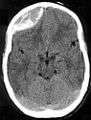

Epidural hematoma. Note the biconvex shape hemorrhage.

On images produced by CT scans and MRIs, epidural hematomas usually appear convex in shape because their expansion stops at the skull's sutures, where the dura mater is tightly attached to the skull. Thus they expand inward toward the brain rather than along the inside of the skull, as occurs in subdural hematoma. The lens-like shape of the hematoma causes the appearance of these bleeds to be "lentiform."